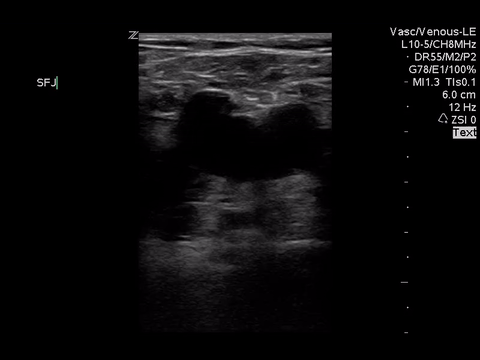

We can eliminate a few diagnoses off the differential with this scan. However, with the diagnosis of PE remaining a 2-point DVT scan was carried out:

Right lower extremity

In each of these images it appears the vein fully collapses with compression. We can conclude that there is likely no DVT present within the limitations of the 2-point compression scan (see discussion for further details)